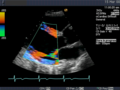

Die Sonografie ist das wichtigste Verfahren bei der Differentialdiagnose eines akuten Abdomens, bei Gallensteinen oder bei der Beurteilung von Gefäßen und deren Durchlässigkeit, vor allem an den Beinen. Weiterhin wird sie standardmäßig zur Untersuchung der Schilddrüse, des Herzens – dann Echokardiografie oder Ultraschallkardiografie (UKG) genannt –, der Nieren, der Harnwege und der Harnblase benutzt. Durch den Einsatz von Echokontrastverstärkern (Kontrastmittel) ist in geeigneten Fällen eine weitere Verbesserung der Diagnostik möglich.

Ihre Hauptanwendung findet diese Untersuchungsmethode in der Echokardiografie, um Bewegungen einzelner Herzmuskelbereiche und der Herzklappen genauer untersuchen zu können. Die zeitliche Auflösung dieses Modus ist bestimmt durch die maximale Wiederholrate der Schallimpulse und beträgt schon bei 20 cm Tiefe über 3 kHz.

-

Anwendung des Doppler-Verfahrens bei einer Herzuntersuchung: Mitralklappeninsuffizienz -

Gewebe-Doppler im Myokard

Eine spezielle Anwendung ist der Gewebe-Doppler (auch Tissue-Doppler), bei dem nicht die Blutflussgeschwindigkeiten, sondern die Geschwindigkeit des Gewebes, insbesondere des Myokards gemessen und dargestellt werden. Gegenüber den herkömmlichen Doppler-Verfahren treten wesentlich geringere Frequenzverschiebungen auf, und daher erfordert diese Untersuchungsmethode besondere Gerätemodifikationen. Eine Anwendung des Gewebe-Dopplers sind Strain (Elastizität) und Strain Rate (Elastizitäts-Rate) Imaging: hier wird die Kontraktilität einzelner Gewebeabschnitte des Herzmuskels gemessen, womit man hofft, bessere Aussagen zur regionalen Wandbewegung machen zu können.[6]